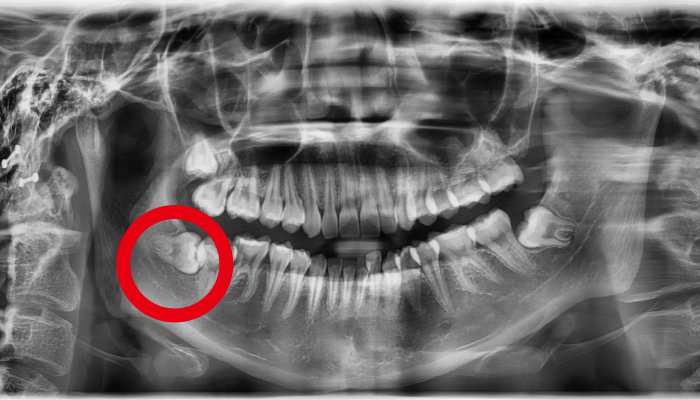

사랑니가 신경과 맞닿아 있는 상황을 제외하고는 안전하고 신속하게 발치가 가능합니다. 사랑니가 비스듬하게 누워있는 경우에는 수술적인 방법을 통해 발치를 해야합니다.

사람에 따라 다르지만 사랑니는 대부분 뼈의 자리가 부족하거나 기울어져 나거나 일부분에만 나오게 되어 관리가 매우 힘들고 인접 치아에 충치까지 유발할 수 있습니다. 매복사랑니는 고난이도 기술이기 떄문에 숙련된 의사의 발치가 중요합니다.

사랑니 발치 전후 사례

• 치료전

치료후